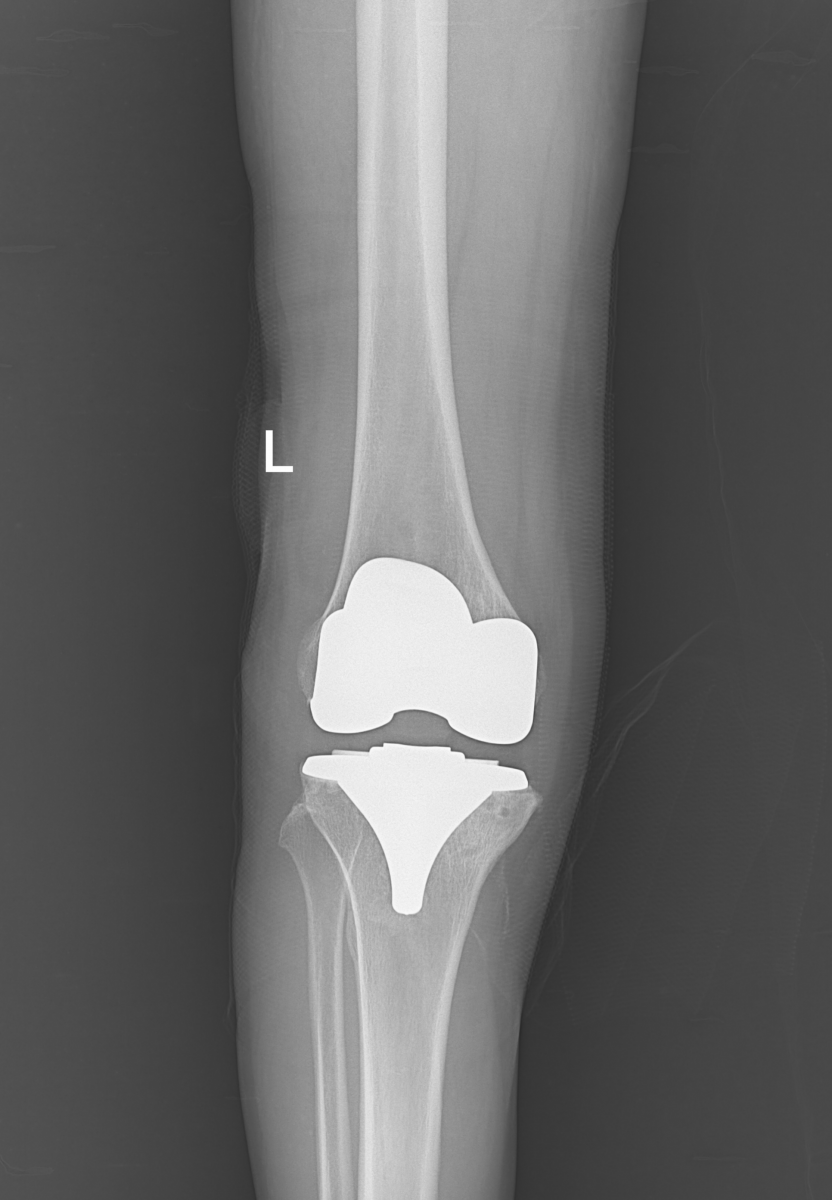

Hình ảnh khớp gối (T) sau khi phẫu thuật của bệnh nhân Trương Thị L.

Sau khi nhập viện và được các bác sỹ thăm khám, hội chẩn, bệnh nhân được chẩn đoán thoái hóa khớp gối (T) độ IV, có chỉ định phẫu thuật thay khớp gối (T) toàn phần.

Được biết, bệnh nhân Trương Thị L. (72 tuổi, địa chỉ xã Thạch Bàn, huyện Thạch Hà) nhập viện và điều trị tại khoa Chấn thương chỉnh hình - Bỏng. Trước đây, bệnh nhân bị đau khớp gối trái và điều trị tại nội khoa đã lâu, tuy nhiên thời gian gần đây khớp gối trái bị đau nhiều hơn, cứng khớp, không thể đi lại được.